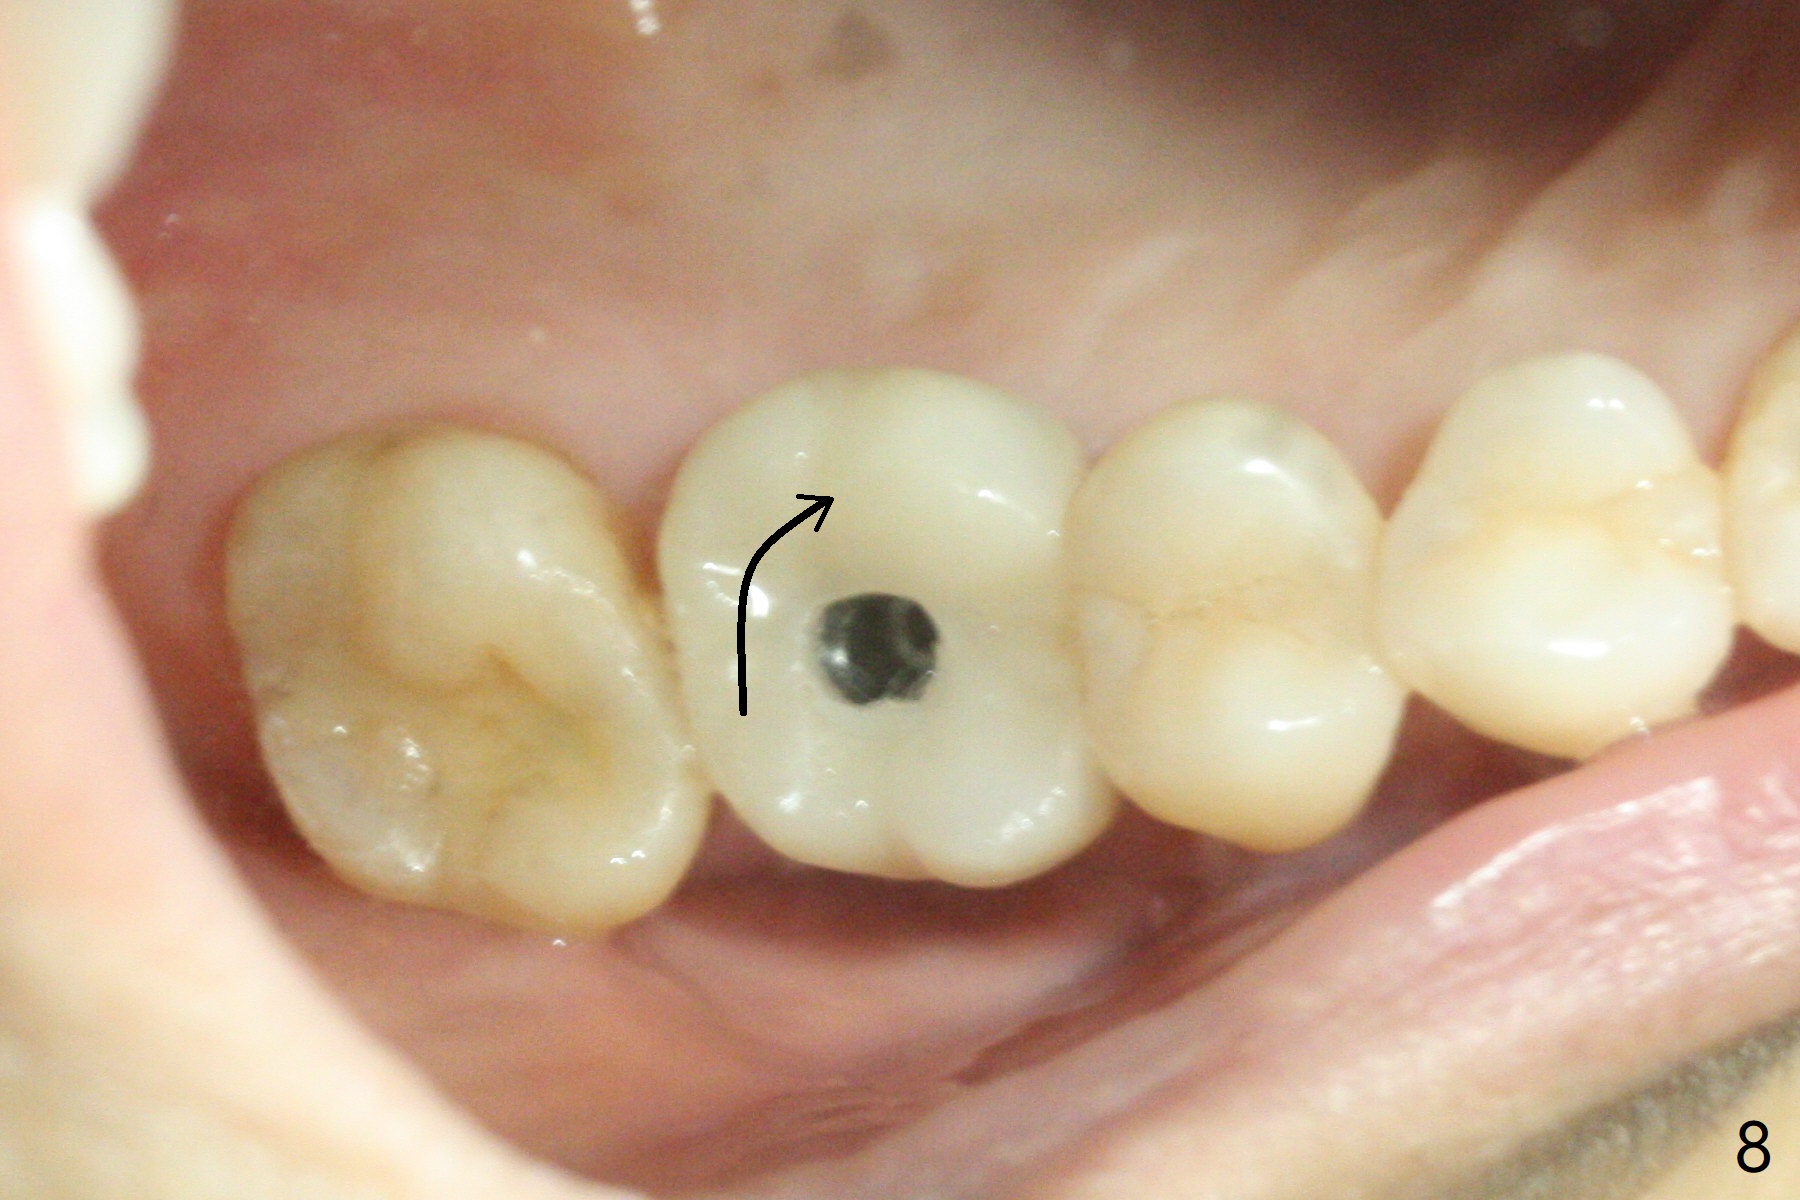

There is mild crestal bone loss 4.5 months postop (Fig.5).  When the patient returns for periodic exam and prophy 6 months post cementation, the crown is found to be loose, which is more likely associated with heavy mastication (long roots) and poor crown/implant ratio.  Since the distal contact is light, the case returns to lab.  PA taken following reseating the repaired abutment/crown shows crestal bone loss, which may be associated with the narrow ridge and/or the loose abutment.  The gingival cuff is less healthy (Fig.6).  The screw becomes loose again 4 months later.  When it is retightened, the distal proximal contact turns open (Fig.7 ^).  The crown appears to turn with the underlying abutment (Fig.8).  After breaking proximal contacts, the crown/abutment is retightened and pick up impression is taken.  It is likely that the abutment was not seated right when abutment-level impression was taken.  The crown table is slightly oversized (Fig.8). Three months later, the screw becomes loose for the 3rd time (unilateral mastication, pain at #19 without RCT).  The abutment hex is not worn.  The crown is removed and the abutment is reseated and torqued 30 Ncm.  Impression is taken for new crown.  The latter is cemented without removing the abutment (Fig.9 (note bone loss)).  In fact the crown/abutment should have been torqued with screw driver buried in place!